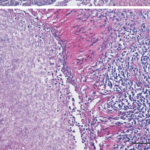

- Hautbiopsie: Eine Biopsie der Läsion ist für die endgültige Diagnose entscheidend. Bei der histopathologischen Untersuchung können die charakteristischen breitbasigen, knospenden Hefen von Blastomyces nachgewiesen werden.

Wenn sich Blastomyces dermatitidis auf der Haut ausbreitet, typischerweise von der Lunge über die Blutbahn, beginnt er, die Hautzellen zu infizieren. Die Hefeform des Pilzes dringt in die Epidermis und manchmal auch in die Dermis ein und führt zu Entzündungsreaktionen. Dies führt zur Bildung von Pusteln, Geschwüren und anderen Läsionen, die die normalen Barriere- und Regulierungsfunktionen der Haut stören.

Die anhaltende Infektion und Entzündung kann weitere Schäden verursachen, da die Fähigkeit der Haut, zu heilen und richtig zu funktionieren, beeinträchtigt wird. Chronische Läsionen können zu Narbenbildung und zum Abbau von Hautgewebe führen, was in schweren Fällen Sekundärinfektionen und andere systemische Komplikationen zur Folge haben kann. Diese Störung beeinträchtigt nicht nur die Schutzfunktion der Haut, sondern kann auch ihre sensorischen und regulatorischen Funktionen beeinträchtigen, was sich erheblich auf die allgemeine Gesundheit auswirkt.